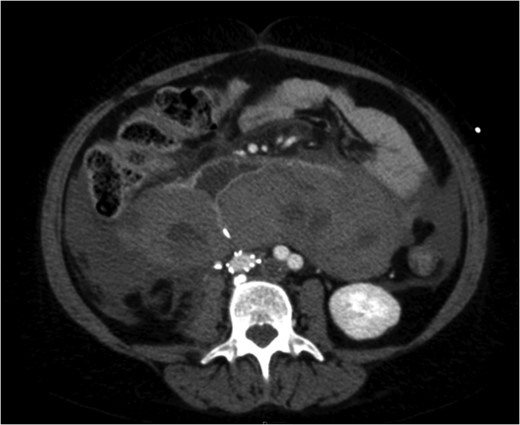

Excessive tilting of the IVC filter causes the hook of the filter to appear outside of the lumen of the IVC.